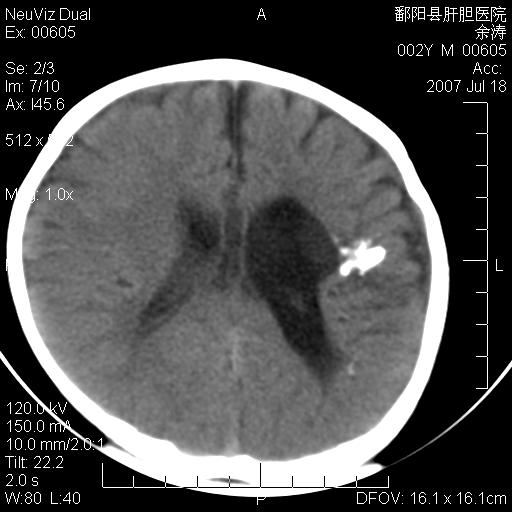

男性 2岁:平时智力障碍。外伤后行颅脑平扫。

左颞叶“萎缩”,可见不规则高密度影,并左侧室扩大,呈负占位效应...支持考虑先天发育异常(血管发育畸形)可能性大,建议结合进一步检查了解。

左颞叶“萎缩”其内可见不规则点条状高密度影,并左侧室扩大,考虑颅面血管瘤病

脑裂畸形;左侧脑脑萎缩;透明隔囊肿;血管畸形?

开唇型脑裂畸形

左侧颞顶叶钙化灶,其内有小片状低密度影 边缘清晰。与之相邻的脑沟增宽增深 ,左侧侧脑室体部牵拉扩大。考虑左颞顶软化灶并局限性脑萎缩。透明隔间腔。